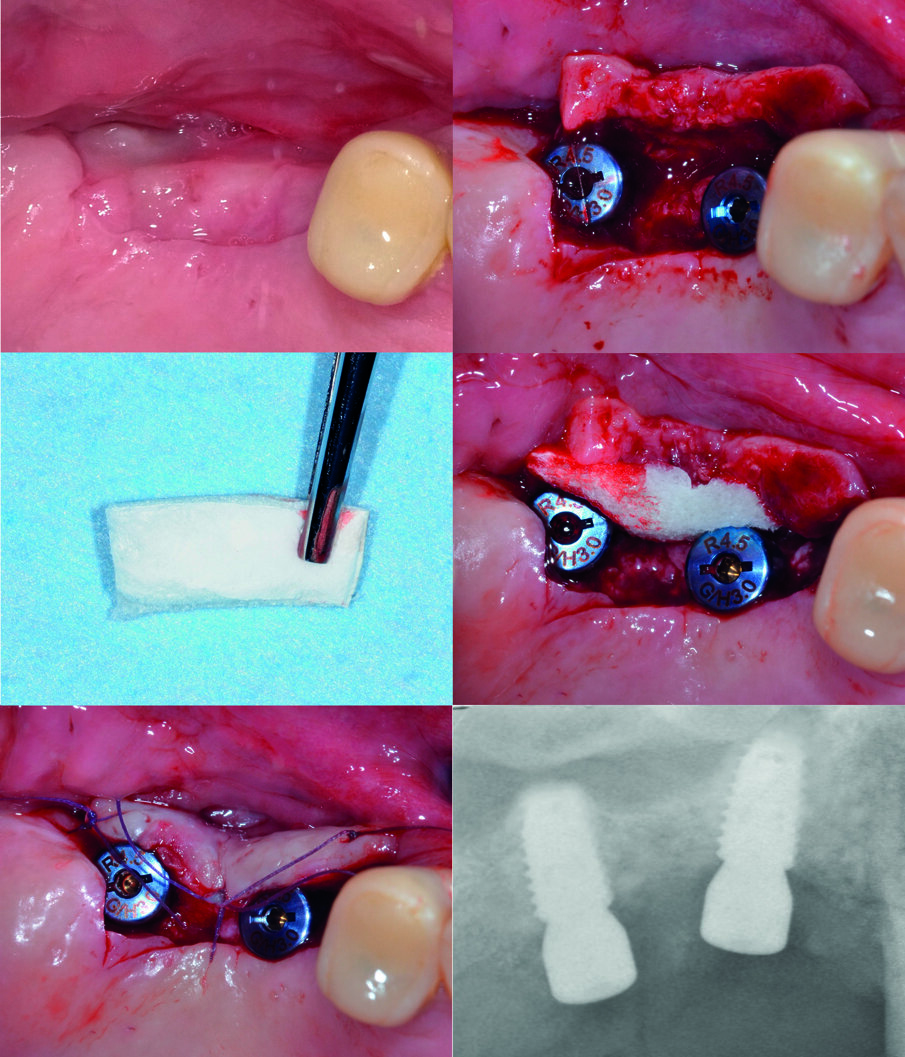

La sutura è stata rimossa 10 giorni dopo. A distanza di sei mesi, gli impianti sono stati scoperti e si è proceduto alla gestione dei tessuti molli perimplantari al fine di ottenere una banda di gengiva aderente adeguata sia in ampiezza che in spessore. A questo fine, oltre a posizionare le viti di guarigione, è stato pianificato un lembo a scivolamento apicale (Fig. 4), sotto il quale, per aumentare ulteriormente lo spessore del tessuto cheratinizzato, è stata innestata una matrice collagenica tridimensionale (BCG-XC50, Xenomatrix, Bioteck S.p.A., Vicenza, Italia), già impiegata con successo per il trattamento delle recessioni gengivali24. Il lembo è stato quindi suturato con punti staccati e si è acquisita una ulteriore radiografia endorale di controllo. Per la successiva riabilitazione protesica il paziente è stato rinviato al collega che lo aveva riferito. Al controllo a 6 mesi la protesi era funzionale e gli impianti osteointegrati, senza segno di riassorbimento osseo perimplantare. Il paziente si dichiarava soddisfatto del risultato dell’intervento.

Fig. 4 - Gestione dei tessuti molli perimplantari. Al fine di ottenere una gengiva aderente di opportuna ampiezza e spessore, dopo avere posizionato le viti di guarigione, viene approntato un lembo a scivolamento apicale sotto il quale è innestata una matrice collagenica tridimensionale.